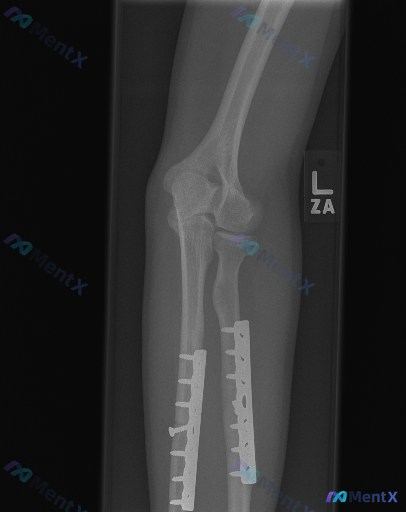

整理到一张左前臂(含肘关节)的X光复查片,先抛出来给大家看看。 影像里明确能看到的: 1. 尺骨和桡骨近段都有金属接骨板+多枚螺钉固定 2. 内固定物位置看起来还稳,没有明显断钉、松动或钢板断裂 3. 肘关节各个关节对位正常,间隙也清 4. 周围软组织没有明显肿胀 但有个细节有点意思: 接骨板覆盖的...